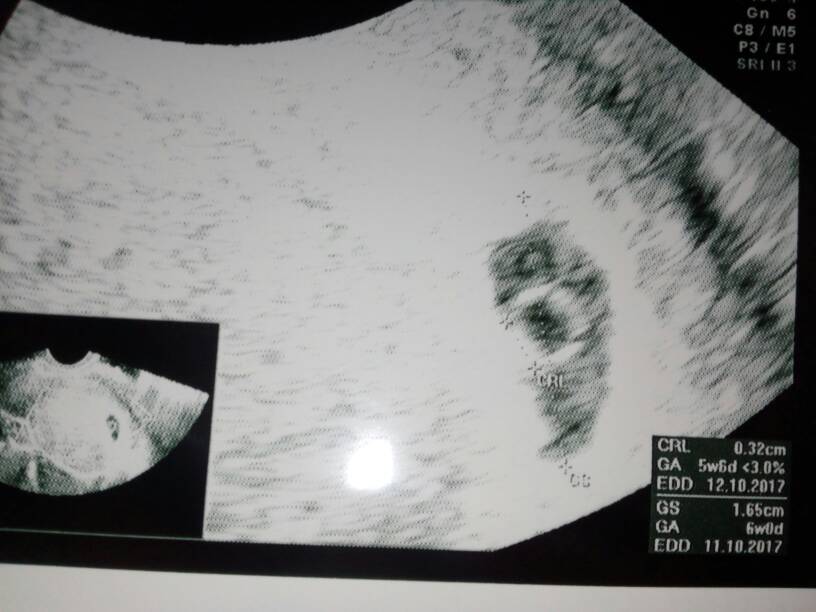

Dzidzia jeszcze młodsza , ale silna , 5t6d , 3.2mm z serduszkiem [emoji171]

5t6d [emoji235]

Bum sliczna fasolka gratuluję [emoji3] ja tez będę miała usg w 5t i 6d.